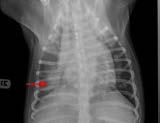

Figura 3. Medición de la presión arterial no invasiva mediante un méto do oscilométrico en un paciente canino con parvovirus. Figura 4. Medidas de bioseguridad para evitar la propagación intra hospitalaria del parvovirus: uso de bata, guantes, calzas y material ex clusivo para estos pacientes. Figura 5. Infección del punto de inyección por catéter intravenoso, con necrosis de la piel y presencia de contenido purulento, en un paciente canino leucopénico por parvovirus. Figura 6. Radiografía de tórax laterolateral de un paciente canino tras la inserción de un catéter venoso central para comprobación de la co rrecta colocación (vena cava craneal).